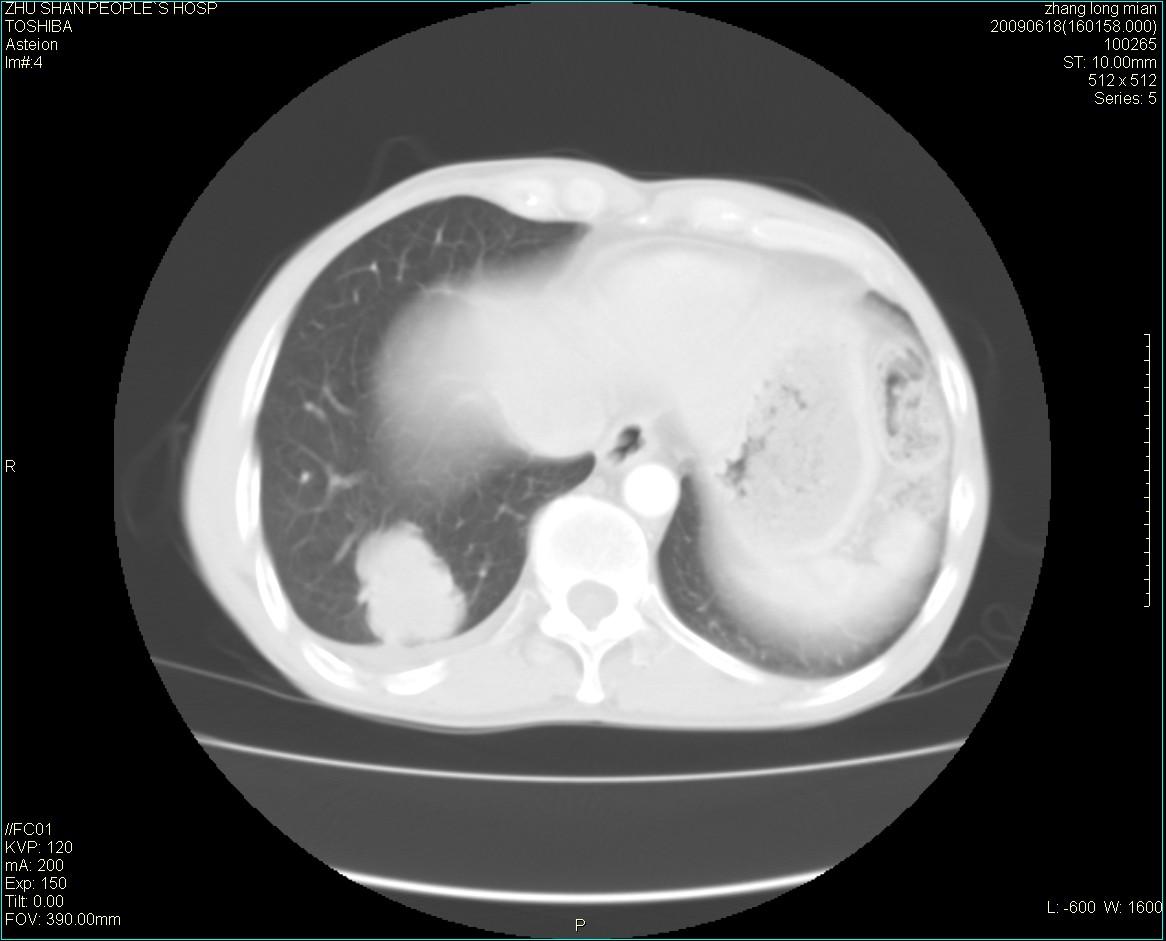

男性 65岁 胸片发现右下肺包块.诊断肺ca并纵隔转移没有问题吧!

两侧胸廓不对称,右侧呈塌陷改变,右肺萎缩。

右下肺见浅分叶状软组织块影,边缘有毛刺,其下部似见不完整偏心空洞影,邻近胸膜凹陷征,并胸腔积液。

增强见纵隔区气管隆突上下及左肺门区肿大淋巴结。左肺感染性病灶。